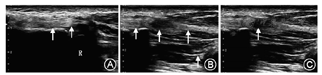

(1)腱鞘切开松解术:手掌部局部浸润麻醉,应用气囊止血带。在掌指关节横纹的近侧做约2 cm长的横切口,切开皮肤及皮下组织,暴露狭窄腱鞘并切开,松解受限的屈指肌腱,屈伸手指,确定松解彻底后,缝合皮肤切口,敷料加压包扎。(2)环线切割手术:①穿刺点选择:以拇长屈肌腱狭窄性腱鞘炎为例,拇指掌指关节过伸,在指掌侧正中拇长屈肌腱膨大结节远端为远端穿刺点,拇指掌指关节横纹近端1.5 cm处为近端穿刺点。两穿刺点选择在指掌侧正中,可避免穿刺点对两侧指固有神经及血管造成损伤。②超声引导下环线切割操作:常规消毒、铺巾,质量浓度为10 g/L的盐酸利多卡因5 ml由远端穿刺点向近端穿刺点分别行腱鞘浅层及深层局部浸润麻醉。麻醉满意后,应用(TC-2021)高频超声诊断仪,使用3~11 MHz超宽频探头,取16号硬脊膜穿刺针在超声引导下,由远端穿刺点向近端穿刺点通过腱鞘的深层穿针,取出针芯,引入切割线(手术切割线为直径1.0 mm的全螺纹切割线Ridge&Crest,美国)。退出穿刺针,将切割线留置于鞘管内。再次由远端穿刺点向近端穿刺点通过腱鞘的浅层穿针,取出针芯,将留置切割线远端引入针芯并向远端抽出,使切割线环套腱鞘。切割线一部分位于鞘管内部,另一部分位于腱鞘表面,环绕腱鞘。反复牵拉切割线,使之切断腱鞘。术中超声观察手术前后拇长屈肌腱滑动状态的改变以及腱鞘切开后的断端(图1,图2)。术后无需缝合,无菌敷料加压包扎,24 h后可拆除敷料。拆除敷料后可逐渐开始拇指屈伸功能锻炼。

环线切割手术的操作注意事项包括: (1)熟悉局部解剖结构:术者必须熟悉掌指关节部腱周解剖结构,控制穿刺针的深度及方向,避免两侧的神经及血管损伤,该技术也有一定的学习曲线,初学者可以由助手协助固定和过伸掌指关节,熟练后可以单人操作。(2)穿刺点的定位:取掌指关节过伸位易于穿刺针的穿出,避免穿入肌腱内,两穿刺点位于指掌侧中点即可避免两侧神经及血管损伤。(3)超声影像的辅助:术中水平切面超声可见圆形的指屈肌腱,环线位于肌腱表浅正中位置,纵向切面超声可见增厚腱鞘被切割线环套,腱鞘切断的观察:腱鞘切断后超声可见断端缺口,确定腱鞘已被切断。初学者可先在正常指观察肌腱结构,正常A1滑车需仔细鉴别。但是在患指通过触诊屈指肌腱增大结节,同时记号笔标记结节近端A1滑车部位,准确的解剖标志结合B超可清晰鉴别肥厚的滑车。